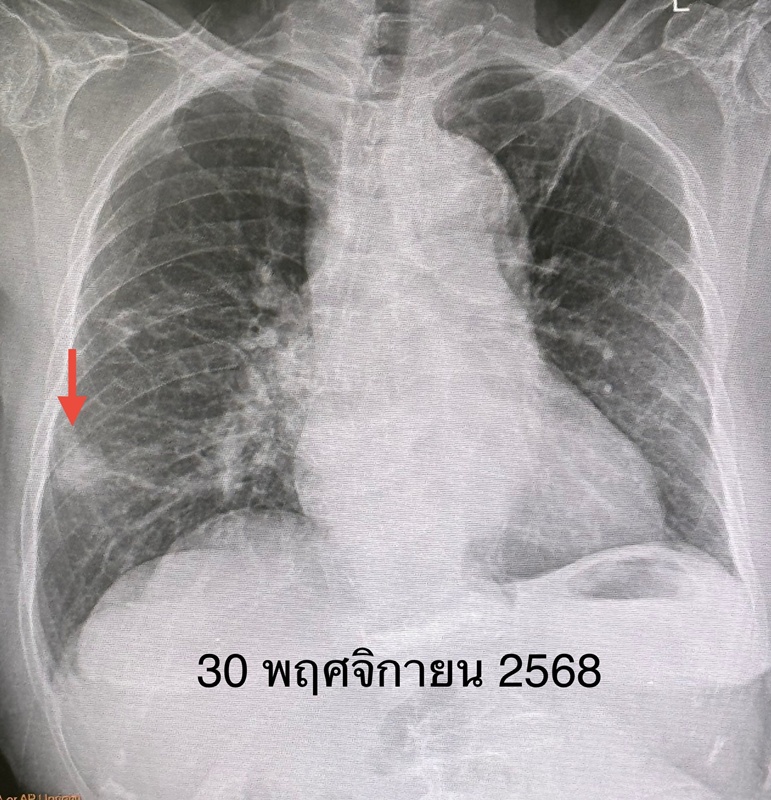

ผู้ป่วยรายนี้ มาตรวจร่างกายประจำปี ตรวจร่างกาย ไม่มีไข้ ฟังปอดปกติ เอกซเรย์ปอด มีเงาผิดปกติปอดข้างขวาด้านบนจากเคยป่วยเป็นวัณโรค และมีก้อนขนาด 1.9 x 1.9 เซนติเมตรที่ปอดข้างขวาด้านล่าง (ดูรูป) ก้อนนี้เป็นก้อนใหม่เพิ่งพบครั้งแรก ปีที่แล้วไม่มีก้อน ทำคอมพิวเตอร์ปอด พบก้อนขนาด 3.0 × 2.4 × 2.0 เซนติเมตรที่ปอดข้างขวาด้านล่าง ตรวจเลือด ค่ามะเร็งทุกตัวปกติ